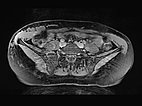

Transverse, T2-weighted, fat-suppressed MRI at the level of the iliac crest shows additional extension of the lymphatic malformation to the right flank. Only the epifascial portions of the abdominal wall and trunk wall are involved.